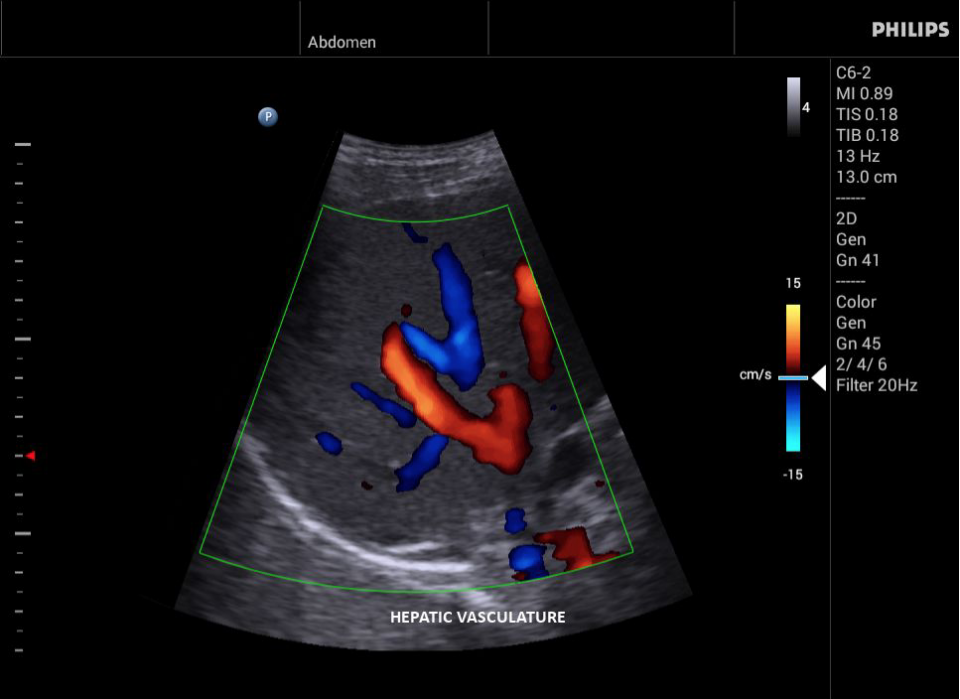

• Конвексный УЗИ датчик Philips С6-2

• Цветное допплеровское картирование

• Исследования сосудов;